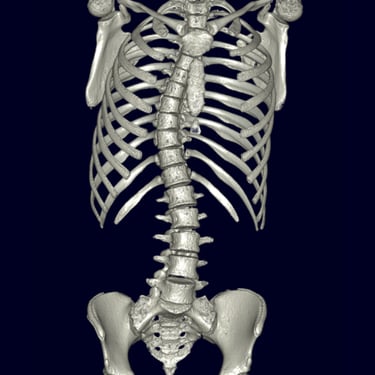

La escoliosis del adolescente idiopática del es una curvatura anormal de la columna vertebral que aparece durante el crecimiento, sin causa identificable. Su diagnóstico se realiza mediante evaluación clínica y estudios por imágenes, principalmente radiografías de columna completa, que permiten medir el ángulo de Cobb y determinar la magnitud de la desviación. En casos complejos o con sospecha de compromiso neurológico, se utiliza resonancia magnética para descartar anomalías medulares. La detección temprana es clave para definir el tratamiento adecuado —observación, uso de corsé o cirugía— y prevenir la progresión de la deformidad.